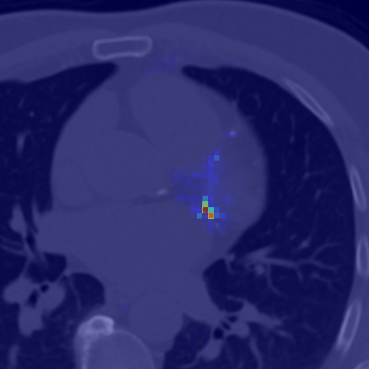

Refer to caption

(a)

(b)

(c)

(d)

Figure 3: Representation of generated features by DINO-LG model trained with label-guided approach and standard DINO training. Figure (a)𝑎(a)( italic_a ) represents a CT slice having calcified area and (b)𝑏(b)( italic_b ) shows annotated area for calcification. Figure (c)𝑐(c)( italic_c ) and (d)𝑑(d)( italic_d ) represent visualization of overlay self-attention maps are generated by standard DINO model and DINO-LG model, respectively.

Label-guided augmentation is effective for the data with only labels or prompt points. During the training phase, CT slices with annotations or labels are randomly augmented regardless of whether they have labels. In addition to this random augmentation, it is applied an augmentation which centers the center of annotated areas chosen randomly from labels. This point specific augmentation helps the model to emphasize on that labeled areas more than other randomly chosen and cropped areas. The point specific data augmentation or label-guided data augmentation has been applied for local data augmentations rather than global data augmentation, as the areas we want to highlight in features generated by DINO contain more localized information. The Fig. 2 represents locally guided data augmentation on a CT slice which includes a calcification. In our experiments, random local data augmentation was set to 8888, while guided local data augmentation was set to 6666, in order to preserve the randomness of the local data augmentation process. To illustrate the contributions of guided data augmentation, Fig. 3 presents a visualization of the outputs from the self-attention heads of DINO models trained using both label-guided and standard methods.